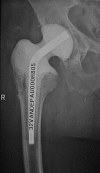

Two-stage revisions with antibiotic-loaded spacers have gained popularity for treating infected hip-joint arthroplasties. The aim of this prospective study was to assess patient functionality between stages and treatment impact on duration of hospital stay and to describe related complications. Sixty-one consecutive patients with infected hip arthroplasties underwent two-stage revision with preformed spacer implantation. Mean Harris Hip and Merle d'Aubigné scores between the two stages were 39.9 and 7.6, respectively. Forty-six patients (75.4%) were able to leave hospital between stages. Spacer dislocation occurred in 16.4%. No cases of spacer breakage were noted. Preformed cement spacers provide acceptable functional outcome between revision hip arthroplasty stages and facilitate the surgical procedure without increasing mechanical complication rates.